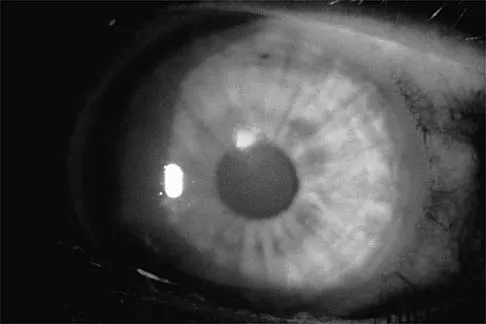

A college basketball player is struck in the eye by a player's hand while driving to the basket. Fluorescein evaluation reveals the injury shown in Figure 18. Management should consist of

Explanation